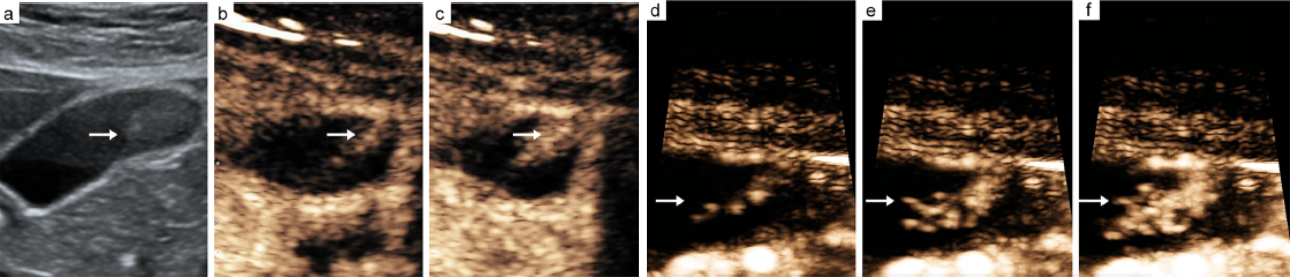

--CEUS images of a gallbladder adenoma show single vascular type (b, c).

--H-CEUS images of a Gallbladder adenoma show branch-like vascular type (d, e, f).

The arrow indicates the vascular type of a gallbladder adenoma